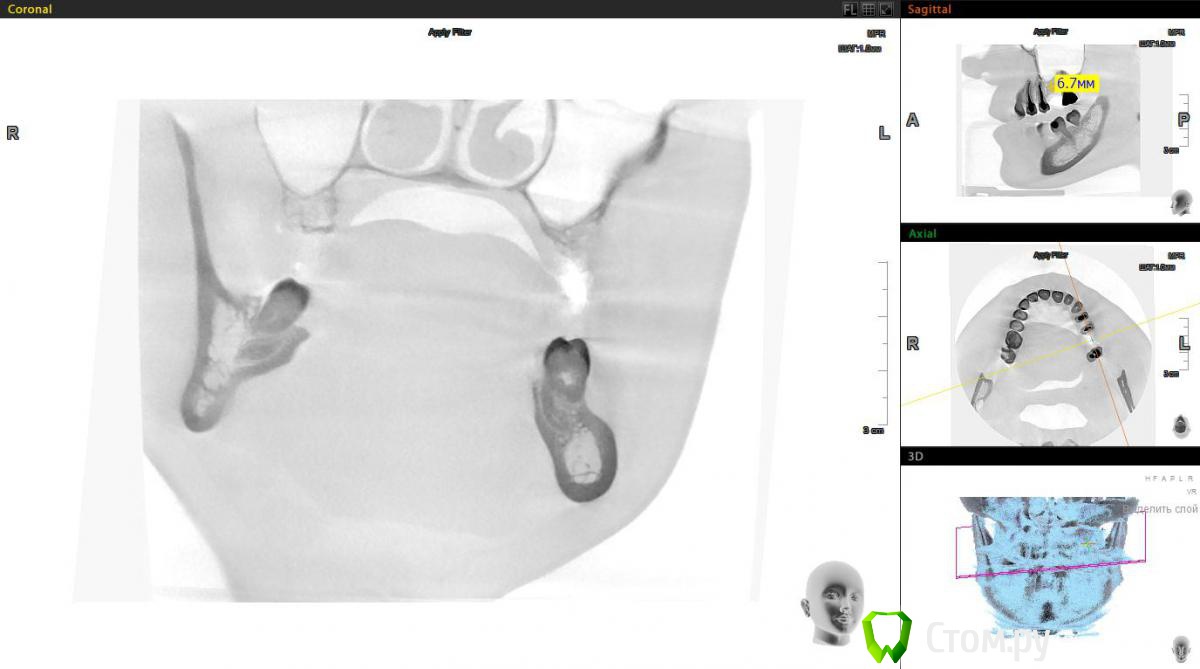

Евгений Ходыкин Опубликовано 1 ноября, 2014 Поделиться Опубликовано 1 ноября, 2014 Есть большое желание обойтись закрытым синусом в данной области. Ложе подготовить экспандерами, ими же поднять "дно". МР3 в пазуху (или чисто на сгустке оставить?). НРК по ситуации. Заранее спасибо за комменты Ссылка на комментарий

Евгений Ходыкин Опубликовано 1 ноября, 2014 Автор Поделиться Опубликовано 1 ноября, 2014 Колеблюсь между 8 и 10 длиной винта Ссылка на комментарий

red_butler Опубликовано 1 ноября, 2014 Поделиться Опубликовано 1 ноября, 2014 Есть большое желание обойтись закрытым синусом в данной области. Ложе подготовить экспандерами, ими же поднять "дно". МР3 в пазуху (или чисто на сгустке оставить?). НРК по ситуации. Заранее спасибо за комменты мне кажется замеры сделаны не корректно, вы мерили от края гребня.реальная высота около 3 мм, соответственно делать нужно открытый Ссылка на комментарий

Евгений Ходыкин Опубликовано 1 ноября, 2014 Автор Поделиться Опубликовано 1 ноября, 2014 Его еще и видно-то плохо. Сделал скрин с инверсией еще Ссылка на комментарий